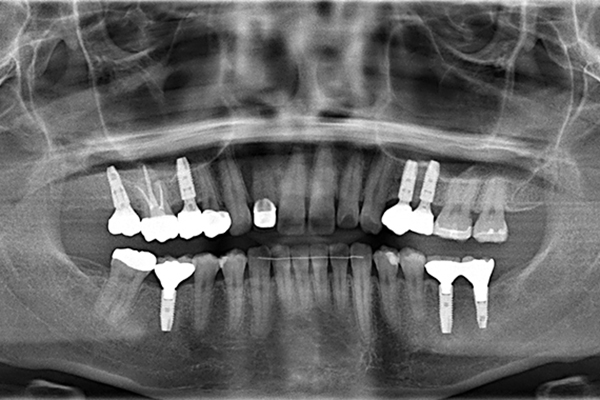

インプラント治療

CTシミュレーションシステムを用いた最先端のデジタルインプラント治療を学ぶことができます。

だからこそ、従来の二次元レントゲンでは不可能な立体での把握で予知性の高い診断を可能にし、インプラント治療や歯科矯正治療などの高度治療のシミュレーションにも貢献する歯科用CTを導入しています。